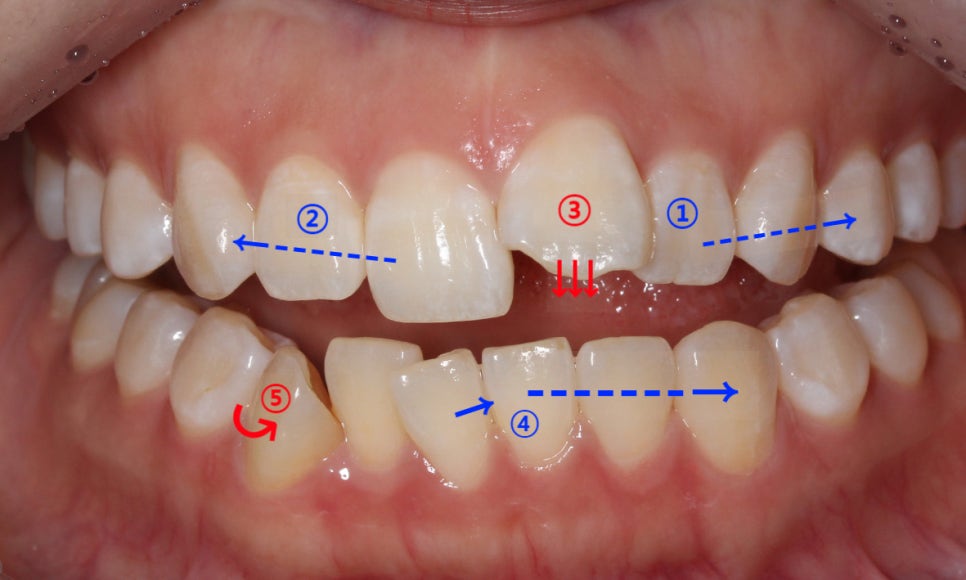

앞니돌출 급속교정 case의 치아의 이동 계획을 보면

상악 20번대 치아의 crowding을 해결하여 공간확보

상악 10번대의 치아의 각도조절

뻐드러진 21번 치아를 설측으로 당겨 앞니돌출 해결

하악의 틀어진 치아들을 바른 각도로 교정

4번으로 확보한 악궁 길이에 맞춰 회전된 송곳니를 바르게 배열함

와 같은 순서로 급속교정 치료가 진행될 예정입니다.

(치료과정을 간략히 설명한 것으로 치아의 이동 상황에 따라

급속교정 계획이 변동될 수 있습니다.)